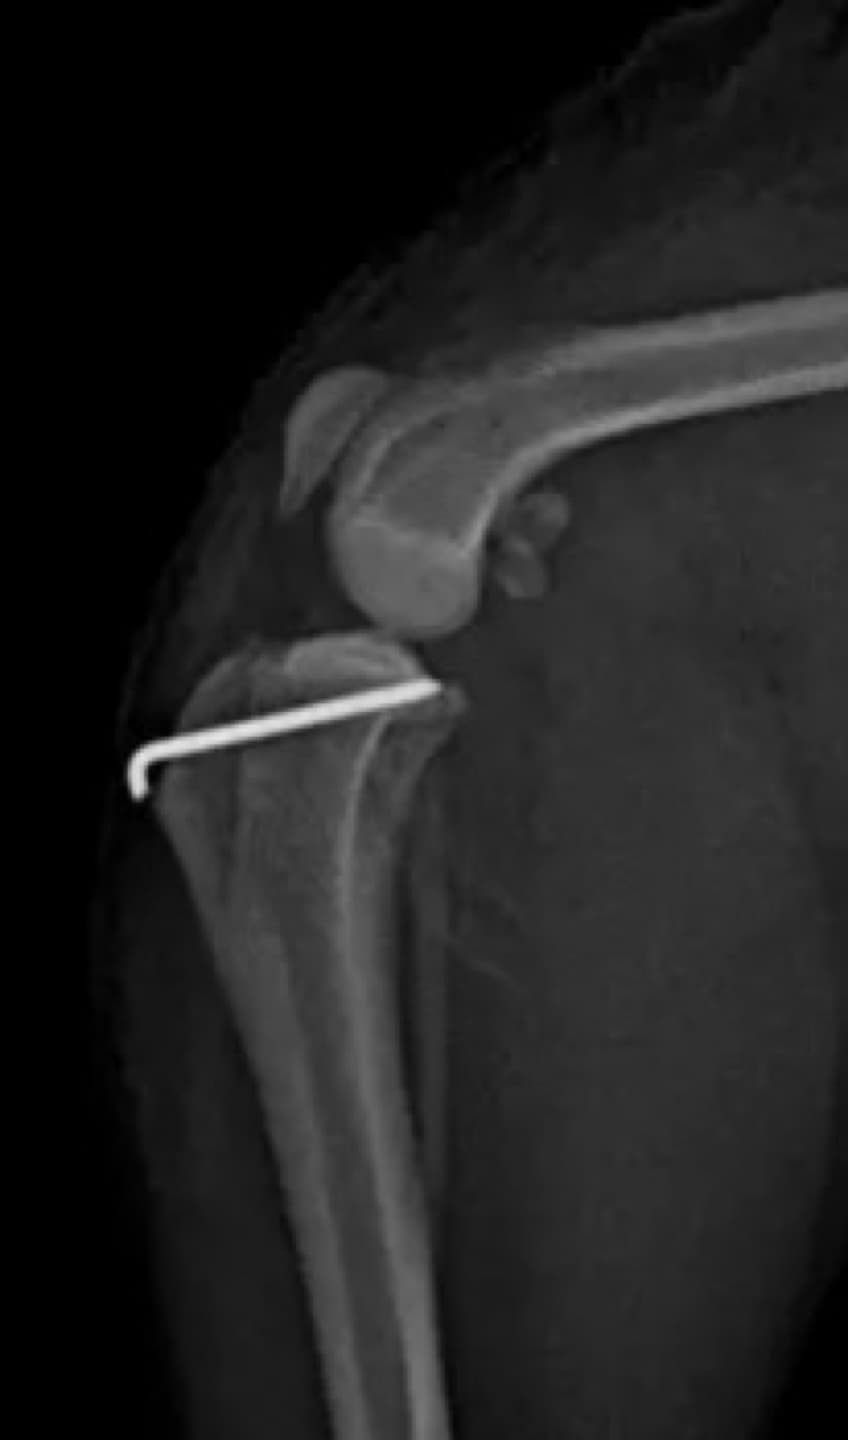

13수술 중 골절 상태 혹은 이식물 적용 후 상태 등 육안으로 명확히 확인하기 힘든 상태를 X-ray 확인하여 정확한 수술 결과를 만들어 내는 것이 가능